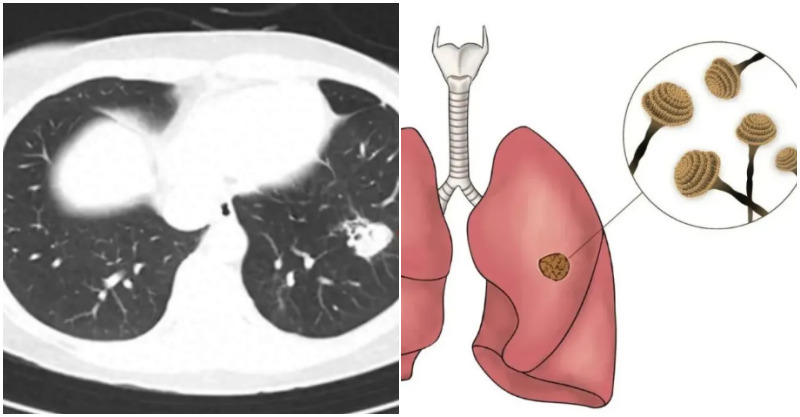

在接診的相關患者中,約有一半患者的腫瘤來自葡萄胎,30%來自流產,10%來自足月妊娠,10%來自子宮外孕。據臨床統計數據,葡萄胎患者中,約有15%-25%會惡性化為滋養細胞腫瘤。「由於其臨床生物學行為特殊,早期易發生轉移,尤其是轉移至肺、肝、腦等重要臟器後,會出現相應器官的症狀,臨床上延誤診治的情況時有發生。」

之後王女士轉至浙江大學醫學院附屬婦產科醫院,接受進一步治療,經過近兩年的化療和免疫治療,狀況才逐漸穩定,目前已經恢復了正常生活。醫生提到,妊娠滋養細胞腫瘤有兩個特點:第一,有非常敏感的腫瘤標記物,即血清HCG的定量檢測;第二、是對化療敏感,因此確診後不必急於手術,而對部分患者,手術可作為輔助手段。

隨著化療藥物的發展,滋養細胞腫瘤的治療效果顯著改善,低危險群患者治癒率接近100%。對於不明原因HCG水平異常升高、且排除妊娠的女性,有葡萄胎史的女性以及出現不明原因腹痛、陰道流血或呼吸困難等症狀的患者,必須警惕,及時就醫,進一步評估是否存在妊娠滋養細胞疾病及腫瘤。